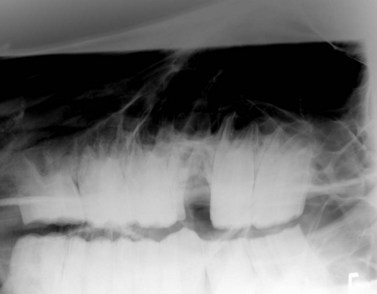

Removing dental fragments can be difficult because often no portion of the tooth is visible supra-gingivally, and because access to the apical aspect of the alveolus, especially one of a young horse, is poor using an oral approach. The dental fragments should be clearly identified on radiographs (Figs 20.26 & 20.27) and then, if possible, elevated per os using long, right-angled elevators (Fig. 20.28). After the fragments are loosened, they can be extracted with right-angled forceps; endoscopic guidance greatly facilitates their removal. When dental fragments or fractured teeth cannot be extracted orally, they can be repulsed using a special root fragment punch or Steinmann pin (Figs 20.2920.31). Radiographic or fluoroscopic guidance may aid the approach to the retained fragments. A 4-mm osteotomy is created over the retained fragment using a Steinmann pin or drill bit, and the Steinmann pin or a root fragment punch is inserted into the osteotomy so that it contacts the fragment. If the pin or punch is positioned properly, the fragment can usually be repulsed into the oral cavity with little force. The alveolus is cleaned of debris, using a spoon curette, and irrigated. The skin incision over the osteotomy is left unsutured to heal by second intention.

Fig. 20.27 Radiograph showing dental fragment in the apex of a mandibular alveolus. The tooth was fractured during an attempt at extraction per os. Dental fragments in the alveolus of a young horse can be difficult to remove, but with careful perioperative imaging to ensure accuracy of the placement of the punch, the fragment can be repulsed into the oral cavity with the horse sedated after desensitizing the affected region with a regional nerve block.